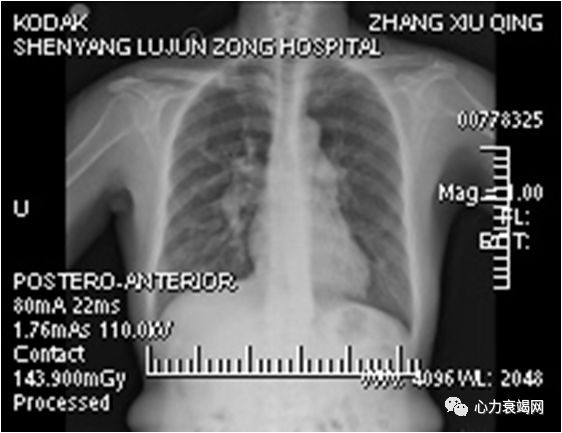

双肺纹理增强增粗,右肺动脉扩张,肺门影增大,心影不大

C/T 0.47